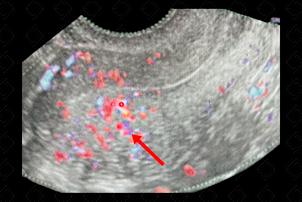

Texto alternativo para a imagem Figura 1. Créditos: Dra. Elazir Mota - Rio de Janeiro/RJ

Descrição da figura 1: Ultrassonografia pélvica (transvaginal), de paciente com quadro de dismenorreia, evidenciando espessamento assimétrico da zona juncional (seta vermelha - indicando lado mais espessado) e com vascularização translesional (ou seja, vasos atravessam a área de espessamento, sem desvios).

• Ultrassonografia pélvica (sendo preferível, quando possível, a realização por via transvaginal): Espessamento assimétrico da zona juncional, áreas císticas focais, ilhas ecogênicas subendometriais, sombra de chuvisco e ao color Doppler, vascularização translesional (f igura 1);